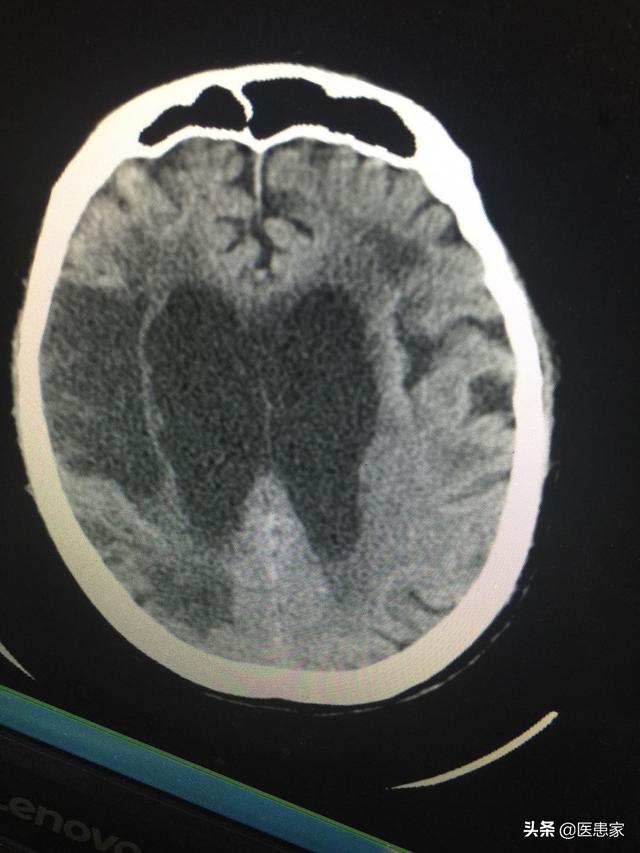

脳梗塞は、脳の一部の動脈血流の異常により低酸素状態となり、血液供給が不十分な部分に欠損が生じ、脳組織の軟化や壊死、失語症や片麻痺などの症状を引き起こす。関連研究によると、発症後24~48時間後に、脳CTによって患部に低密度の病巣が観察される。また、脳梗塞は脳MRIで時間差で発見できる。脳梗塞の臨床症状は、めまい、昏睡、失語症、吐き気などであり、消化管出血、脳血管障害後うつ病、肺感染症、不安症などの合併症を伴う。

脳梗塞の診断は、病歴と症状に基づいて、CT、MRI、デジタルサブトラクションで確定または鑑別される。